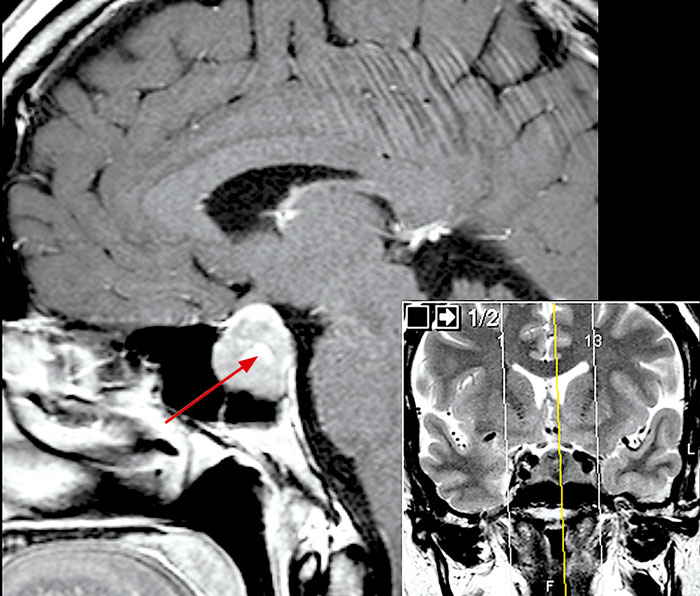

Fallrapport 4 [60] (Fakta 1) rör en 43-årig man som sökte med svår skärande/sprängande smärta sedan två månader. Huvudvärken kom i attacker och satt bakom vänster orbita och vid tinningen. Klinisk undersökning/laboratorieprov var u a. Patienten uppfyllde kriterierna för klusterhuvudvärk, och terapi med sumatriptan i tablett- och injektionsform sattes in. Patienten ville avvakta med förebyggande behandling. Han svarade på injektionsbehandlingen med betydande minskning av huvudvärken inom 20 minuter. Attackfrekvensen minskade också något. Eftersom han inte blev helt bra sökte han igen efter en månad. Förnyad klinisk undersökning var normal. MR hjärna med kontrast beställdes och visade en intra-/suprasellär cysta med expansiv effekt på omgivande strukturer (Figur 4). Operation utfördes, och PAD bekräftade en benign araknoidalcysta. Huvudvärken försvann helt efter operationen och läkemedlen seponerades.

Figur 4. MR hjärna med kontrast, T2-viktade bilder, visar en intra-/suprasellär expansiv araknoidalcysta.